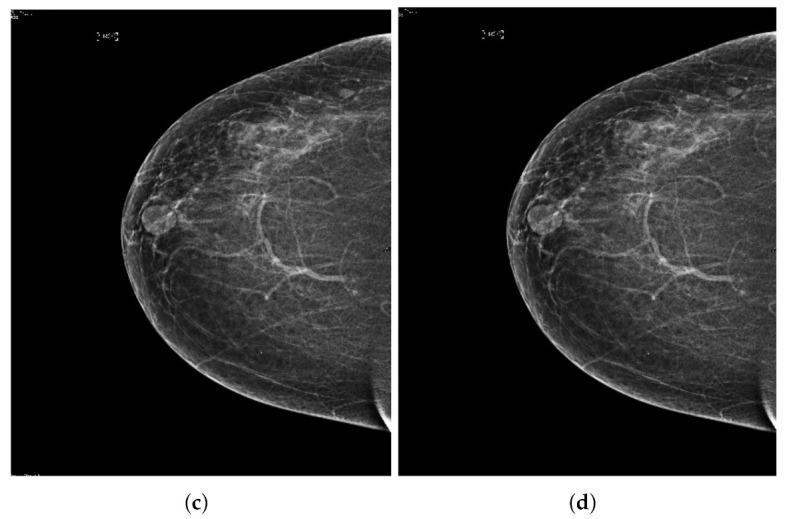

Breast cancer is widespread around the world and can be cured if diagnosed at an early stage. Digital mammograms are used as the most effective imaging modalities for the diagnosis of breast cancer. However, mammography images suffer from low contrast, background noise as well as contrast as non-coherency among the regions, and these factors makes breast cancer diagnosis challenging. These problems can be overcome by using a new image enhancement technique. The objective of this research work is to enhance mammography images to improve the overall process of segmentation and classification of breast cancer diagnosis. We proposed the image enhancement for mammogram images, as well as the ablation of the pectoral muscle. The image enhancement technique involves several steps. In the first step, we process the mammography images in three channels (red, green and blue), the second step is based on the uniformity of the background on morphological operations, and the third step is to obtain a well-contrasted image using principal component analysis (PCA). The fourth step is based on the removal of the pectoral muscle using a seed-based region growth technique, and the last step contains the coherence of the different regions of the image using a second order Gaussian Laplacian (LoG) and an oriented diffusion filter to obtain a much-improved contrast image. The proposed image enhancement technique is tested with our data collected from different hospitals in Qassim health cluster Qassim province Saudi Arabia, and it contains the five Breast Imaging and Reporting System (BI-RADS) categories and this database contained 11,194 images (the images contain carnio-caudal (CC) view and mediolateral oblique(MLO) view of mammography images), and we used approximately 700 images to validate our database. We have achieved improved performance in terms of peak signal-to-noise ratio, contrast, and effective measurement of enhancement (EME) as well as our proposed image enhancement technique outperforms existing image enhancement methods. This performance of our proposed method demonstrates the ability to improve the diagnostic performance of the computerized breast cancer detection method.